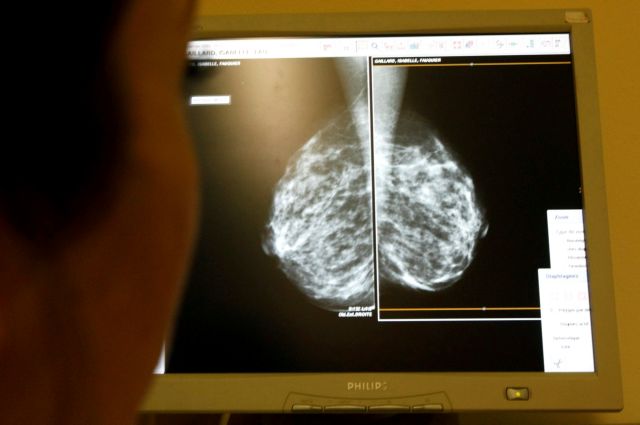

Οι γυναίκες που ακολουθούν θεραπείες ορμονικής υποκατάστασης για να καταπολεμήσουν τις συνέπειες της εμμηνόπαυσης διατρέχουν μεγαλύτερο κίνδυνο εμφάνισης καρκίνου του μαστού, σύμφωνα με νέα επιδημιολογική έρευνα μεγάλης κλίμακας.

Διαπιστώθηκε ότι όλες οι θεραπείες ορμονικής υποκατάστασης (Θ.Ο.Υ) σχετίζονται με αυξημένο κίνδυνο εμφάνισης καρκίνου του μαστού, εξαιρουμένων των τζελ οιστρογόνων που εφαρμόζονται τοπικά.

Έτσι, μια γυναίκα πενήντα ετών που ακολουθεί για αρκετό καιρό Θ.Ο.Υ με οιστρογόνα και προγεστερόνη έχει 8,3% πιθανότητα εμφάνισης καρκίνου του μαστού, τη στιγμή που ο κίνδυνος στο γενικό πληθυσμό των γυναικών που δεν έχουν λάβει θεραπεία είναι 6,3%.

Τα ποσοστά κινδύνου ανάπτυξης καρκίνου του μαστού των γυναικών που ακολούθησαν μια θεραπεία με οιστρογόνα και προγεστερόνη και αυτών που έλαβαν για το ίδιο χρονικό διάστημα μια θεραπεία αποκλειστικά με οιστρογόνα είχαν κίνδυνο 7,7% και 6,8% αντίστοιχα.

Η διάρκεια της θεραπείας, πάντως, φάνηκε να διαδραματίζει σημαντικό ρόλο. «Οι γυναίκες που βρίσκονταν υπό θεραπεία για 10 χρόνια παρουσίαζαν σχεδόν διπλάσιο κίνδυνο από αυτές που έλαβαν θεραπεία για πέντε χρόνια», διευκρινίζει η Τζίλιαν Ριβς, μια από τους συντάκτες της μελέτης από το Πανεπιστήμιο της Οξφόρδης.